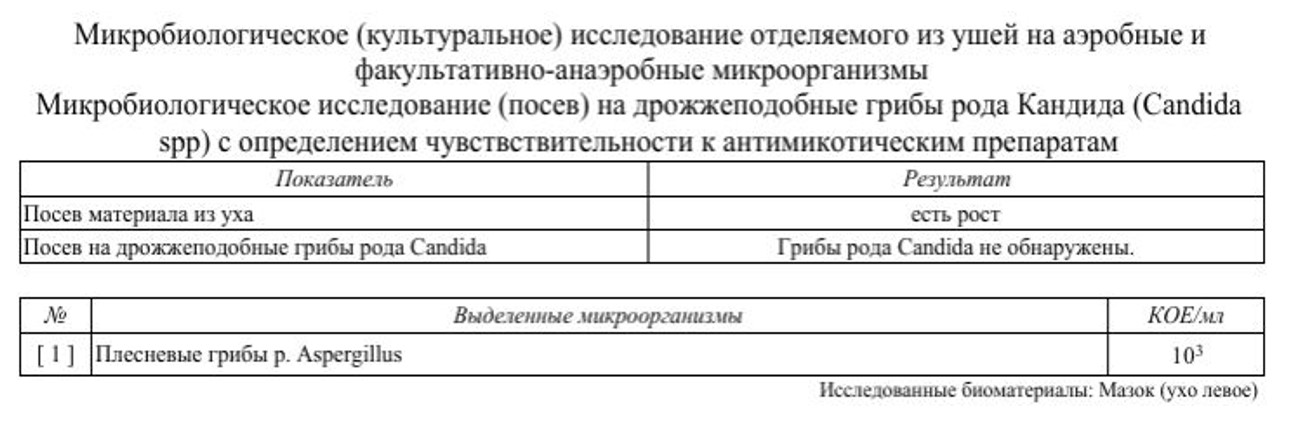

Микробиологическое исследование. Был взят мазок из левого наружного слухового прохода для бактериологического посева с определением чувствительности выделенной флоры к антибиотикам и противогрибковым препаратам. Это необходимо для точного подбора терапии в случае неэффективности стартового лечения. В данном случае получен рост плесневых грибов рода Aspergillus.